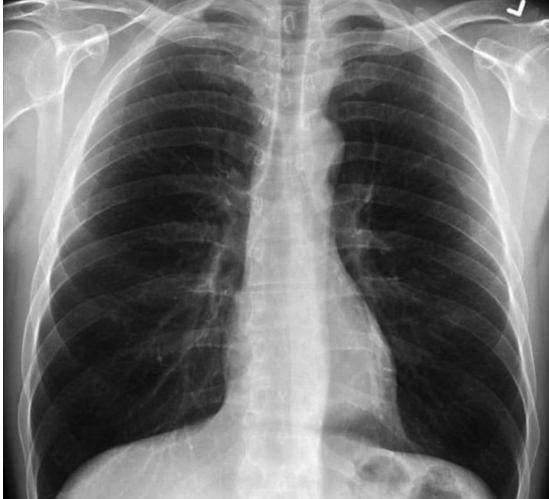

Одно изображение показывает нормальную здоровую пару легких, другое - легкие курильщика, а третье - легкие пациента с коронавирусом.

picture Легкие здорового человека

Нормальные легкие темные и прозрачные, на легких курильщика частично отмечены рубцами, в то время как легкие пациента с коронавирусом почти непрозрачны от повреждений.